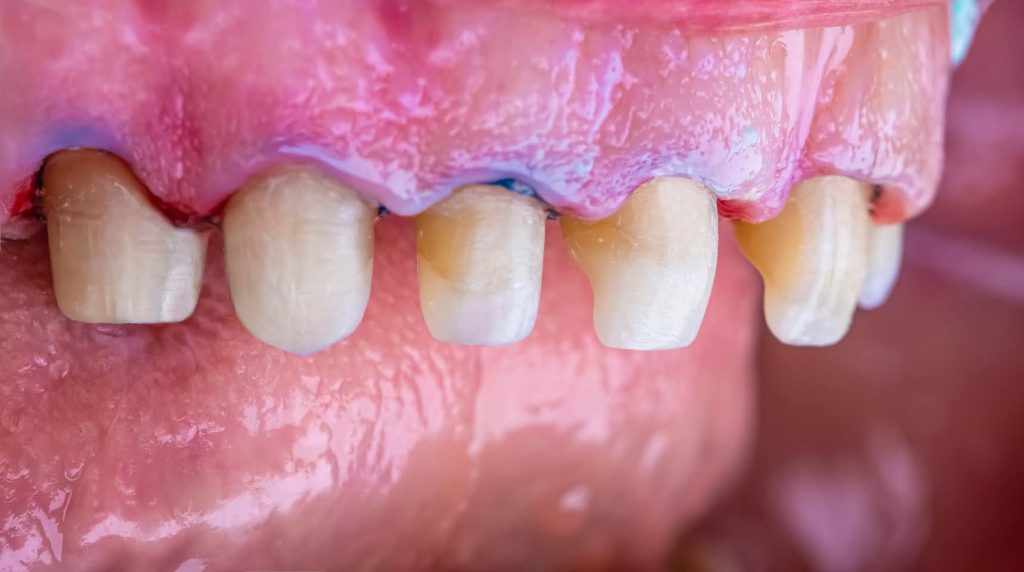

This phase began with the upper arch:

Placement of implants in the free-end areas.

Preparation of teeth and insertion of the fixed prosthesis.